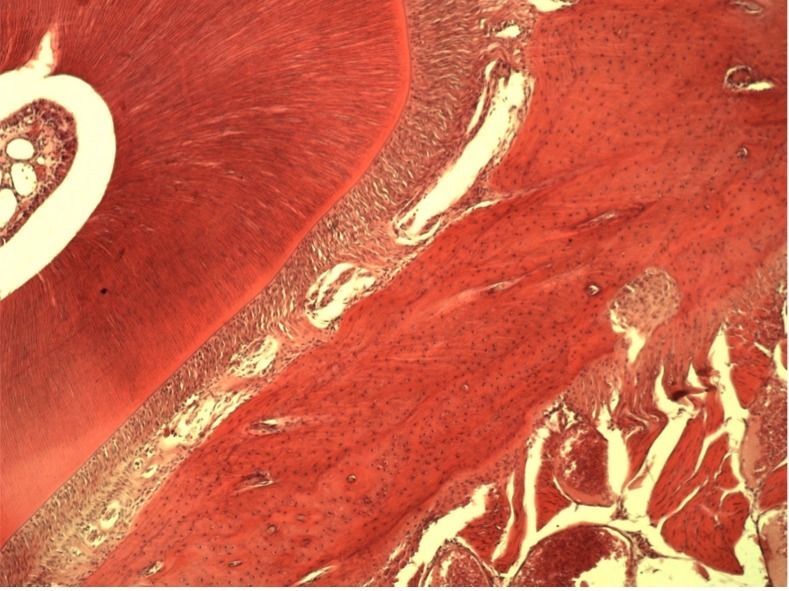

• Минерализованную губчатую или кортикальную кость применяют там, где нужно сохранить объем по высоте и ширине, например, при операции поднятия верхнечелюстного синуса или операции имплантации зубов.

• Деминерализованную кость применяют дополнительно для восстановления внутренних костных дефектов: через нее лучше растут кровеносные сосуды, так как она содержит морфогенетический белок (МГБ), но за счет отсутствия минерального каркаса не способна удержать трехмерный объем.

• Алогенный гидроксиапатит используется при увеличении объема более чем на 5-7 мм по высоте. Возможно поднятие на 12, 13 и даже 15 мм.